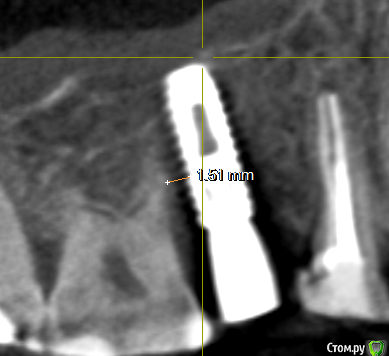

se77777 Опубликовано 10 марта, 2020 Поделиться Опубликовано 10 марта, 2020 (изменено) Здравствуйте, у меня два вопроса в одной теме. 1. Имплант 15 размещен близко к корню зуба и похоже в пазухе. Есть срез с КТ и ссылка на архив с видеофайлами навигации по КТ. Качественно проиграть их можно предварительно загрузив на компьютер.Не знаю, насколько эффективен будет такой формат представления.https://drive.google.com/open?id=1rznLeW8i626T2_lYNk8NwcIDKP171vUxhttps://drive.google.com/open?id=1aSaGx8B-Ch3K6F7t6A5q_t6wTH5SaouQ Какие будут рекомендации? 2. Внезапно и вовремя обнаружилась киста на 47. Есть срез с КТ и ссылка на архив с видеофайлами навигации по КТ.Нечасто и невнятно этот зуб беспокоил всегда. В 2013 лечение каналов, гуттаперча. Киста на снимках не обнаруживалась.После имплантации опять появилась невнятная едва ощутимая боль. https://drive.google.com/open?id=1LvkdNyerYr1ILYWOk6loZPaXm6n-8lRc Зуб можно спасти? Спасибо большое. Архив с КТ в формате Galileos https://drive.google.com/open?id=1WPcDbwztGbDJiXea1Z0jOJty4TklM6pn Попробую достать в Dicom Изменено 10 марта, 2020 пользователем se77777 Ссылка на комментарий

red_butler Опубликовано 10 марта, 2020 Поделиться Опубликовано 10 марта, 2020 Минимальное допустимое расстояние до зуба есть, но сделайте rvg и и фото во рту Ссылка на комментарий